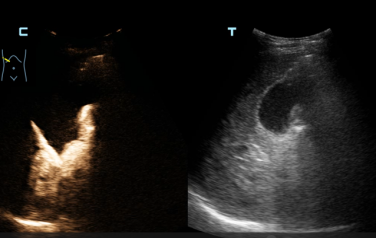

术前面临的主要挑战在于患者左肝胆管位置较高、走行迂曲,可供安全穿刺的窗口极为有限。该院超声科主治医师李西接手后,在超声影像的清晰引导下,对穿刺路径进行了毫米级的精细规划。术中,在超声「导航」下,李西医师手法娴熟,穿刺针在手中游刃有余,精准地避开血管,直抵目标胆管,随即墨绿色的胆汁从针芯流出—「一针」成功!随后,在助手的配合下,李西依次置入导丝和导管。术后即刻行超声造影显示双侧肝内胆管显影,引流管位置理想,胆汁引流通畅。术后患者生命体征平稳,黄疸症状明显缓解。为表达对超声介入团队的高度认可和衷心感谢,患者家属专程送来了锦旗。